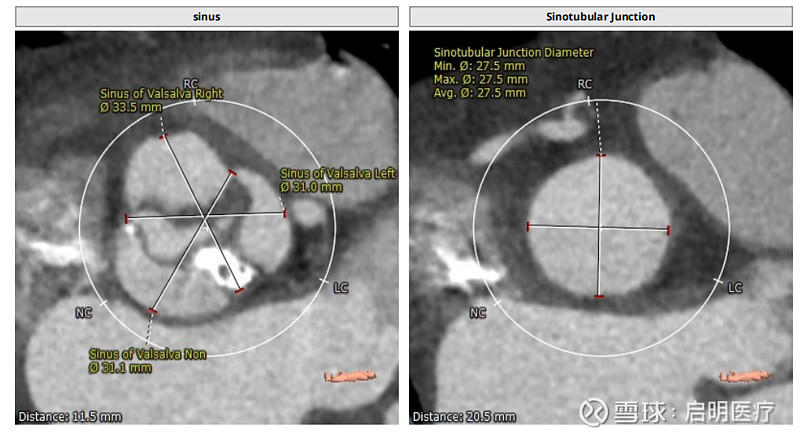

阜外首例二尖瓣与主动脉瓣生物瓣损毁·同期经导管双瓣置换